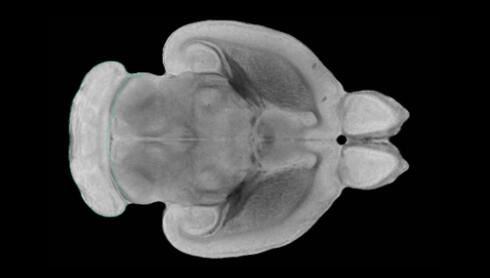

隨著機體年齡增加,肌肉和關(guān)節(jié)都會變得僵硬,這就會使得日?;顒幼兊酶永щy,本文研究表明,我們的大腦也是如此,與年齡相關(guān)的大腦僵硬對大腦干細(xì)胞的功能或許有著重要影響。文章中,研究人員對年輕和老化大鼠的大腦進行研究闡明了年齡相關(guān)大腦僵硬對少突膠質(zhì)前體細(xì)胞(OPCs,oligodendrocyte progenitor cells)功能的影響。OPCs是一類對維持正常大腦功能非常重要的大腦干細(xì)胞,其對于髓磷脂的再生也非常重要,髓磷脂是神經(jīng)組織周圍的脂肪鞘,在多發(fā)性硬化癥中髓磷脂的再生常常會被損傷,機體老化對這些細(xì)胞的影響常常會誘發(fā)多發(fā)性硬化癥的發(fā)生,這些細(xì)胞的功能在老化的健康人群中同樣會下降。

為了確定老化OPCs的功能缺失是否可以被逆轉(zhuǎn),研究人員將來自老化大鼠機體的老化OPCs轉(zhuǎn)移到了年輕大鼠柔軟的海綿狀大腦組織中去,值得注意的是,這些老化的大腦細(xì)胞能夠重新恢復(fù)活力,其行為非常像年輕更加強壯的細(xì)胞。這項研究中,研究人員在實驗室中開發(fā)出了具有可變僵硬程度的新型材料,并在受控環(huán)境下研究這些材料的生長及其對大鼠大腦干細(xì)胞的影響,這些材料能被工程化改造具有和年齡或老化大腦相似的柔軟程度。

為了深入理解大腦組織柔軟和僵硬影響細(xì)胞行為的分子機制,研究人員對細(xì)胞表面一種名為Piezo1的蛋白質(zhì)進行了分析,該蛋白質(zhì)能“告知”細(xì)胞其周圍的環(huán)境為柔軟或僵硬。研究者Kevin Chalut說道,我們發(fā)現(xiàn),當(dāng)在僵硬材料上促進年輕具有功能性的大鼠干細(xì)胞時,這些細(xì)胞就會表現(xiàn)出功能異常,并失去其再生的能力,實際上其行為與老化細(xì)胞相似。當(dāng)將老化的大腦細(xì)胞在柔軟材料上生長時,其功能就會表現(xiàn)得像年輕細(xì)胞一樣,換句話說,其能夠重新恢復(fù)年輕的活力。